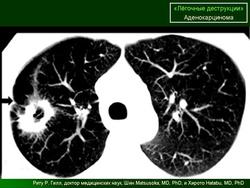

ОГК. Легочные деструкции (кавитации). +

Легочные деструкции (кавитации)

Легочные кавитации. Радиопедия.

Случай 9: кавитирующая аденокарцинома